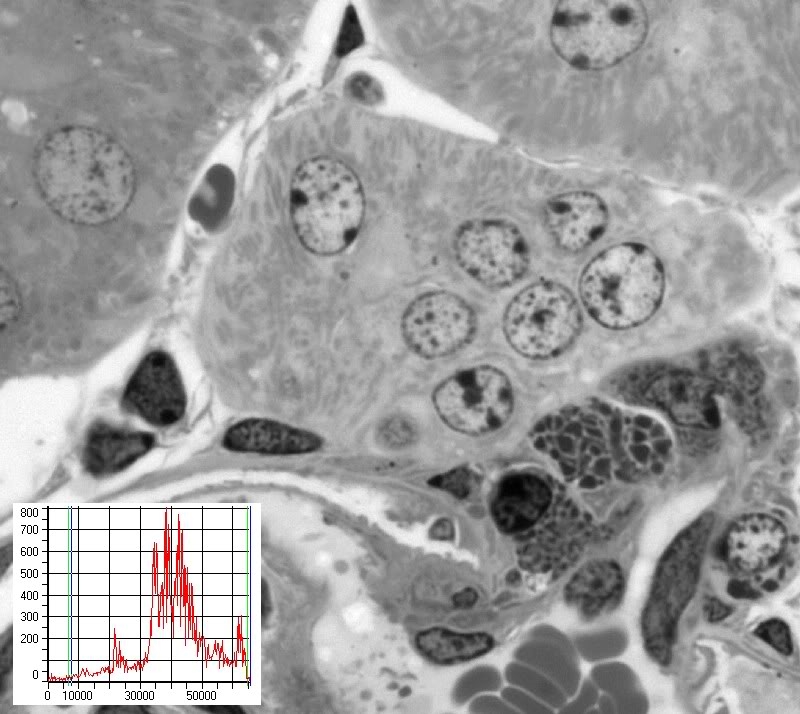

Bild 26a zeigt einen Semidünnschnitt durch Nierengewebe. Das Bild ist RAW, d.h. nicht geschärft und keine Helligkeits, Kontrast oder Gammaanpassungen.

Das in der unteren Ecke angegebene Histogramm zeigt, dass sich eine weitere lineare Kontrastverbesserung verbietet, da die Pixel bereits den gesamten Dynamikumfang des Bildes ausnutzen und somit eine lineare Kontraststeigerung zum Clipping führen würde (Clipping wird in einen früheren Beitrag dieser Serie erklärt).